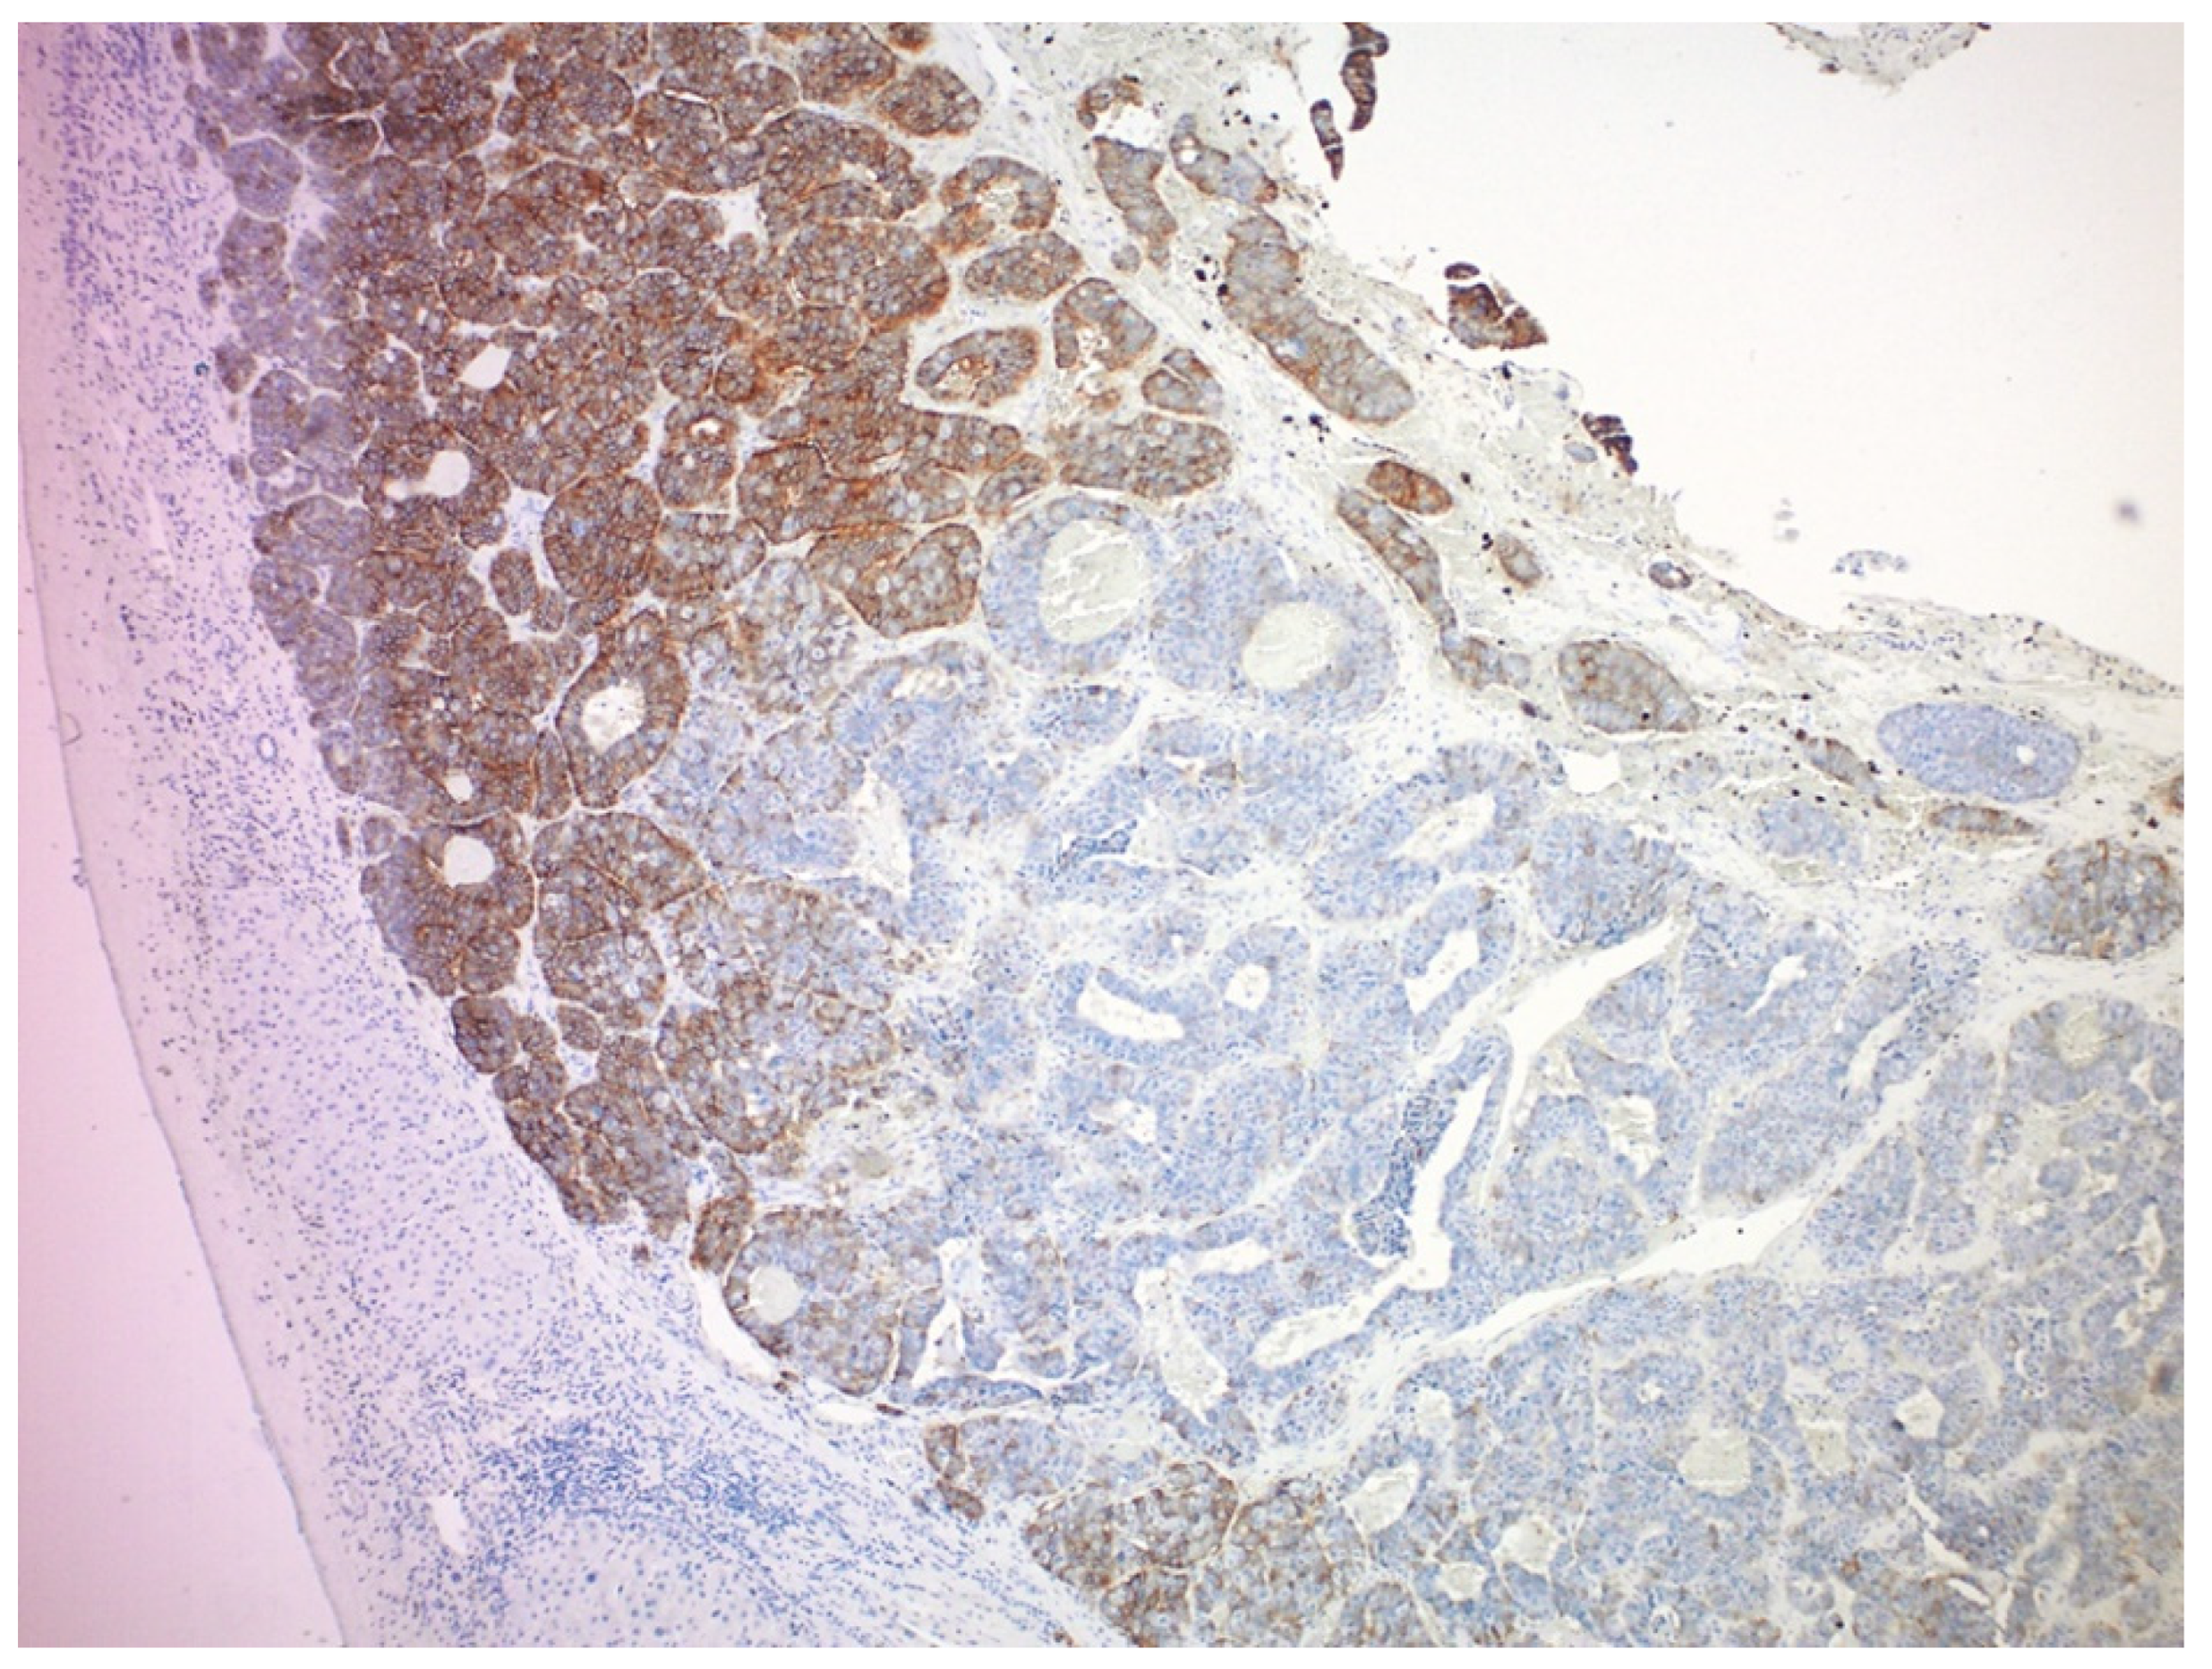

- Charoenpitakchai, M.; Liu, E.; Zhao, Z.; Koyama, T.; Huh, W.J.; Berlin, J.; Hande, K.; Walker, R.; Shi, C. In liver metastases from small intestinal neuroendocrine tumors, SSTR2A expression is heterogeneous. Virchows Arch. 2017, 470, 545–552. [Google Scholar] [CrossRef]